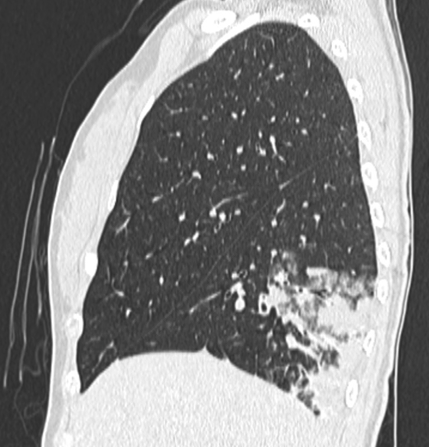

80列マルチスライス撮影により、撮影は約10秒程度です。また、被ばくに対し配慮した設計により、高感度のX線検出器を使用し、低線量、高画質の撮影で安心して検査を受けて頂く事が出来ます。